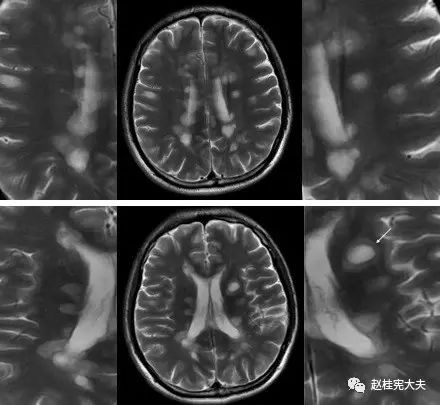

图5. 示双侧放射冠区、侧脑室旁多发圆形、卵圆形或斑片状病灶,T2高信号,部分呈煎蛋征(双娇煎蛋)。(左侧侧脑室旁)病灶长轴与侧脑室长轴垂直。

图6. T2FLAIR薄层示双侧侧脑室旁、胼胝体多发斑片状高信号灶。

多发性斑块在MR上表现为多灶性T1WI等或低信号,T2加权图像(FLAIR序列上尤为明显)上特征性不同程度的高信号,可反映脑灰、白质炎症病变;部分病灶在增强图像上表现为局灶性钆对比增强性信号改变,反映局部急性血脑屏障破坏和活动性炎症反应;较大的活动性斑块在DWI上亦可显示弥散受限。

位于脑室周围典型者,长圆形病灶的长轴与大脑或侧脑室长轴垂直,且有一狭窄正常信号带将病灶与侧脑室分开,而之后转为正常表现的低信号提示髓鞘再生;在疾病晚期,病变可发生融合,T2上出现融合性高信号灶,易误为肿瘤;因病灶可沿室管膜静脉从脑室表面进入邻近白质,故胼胝体常首当其冲罹病,且好发于胼胝体内侧或深部,即靠近脑室边缘处。